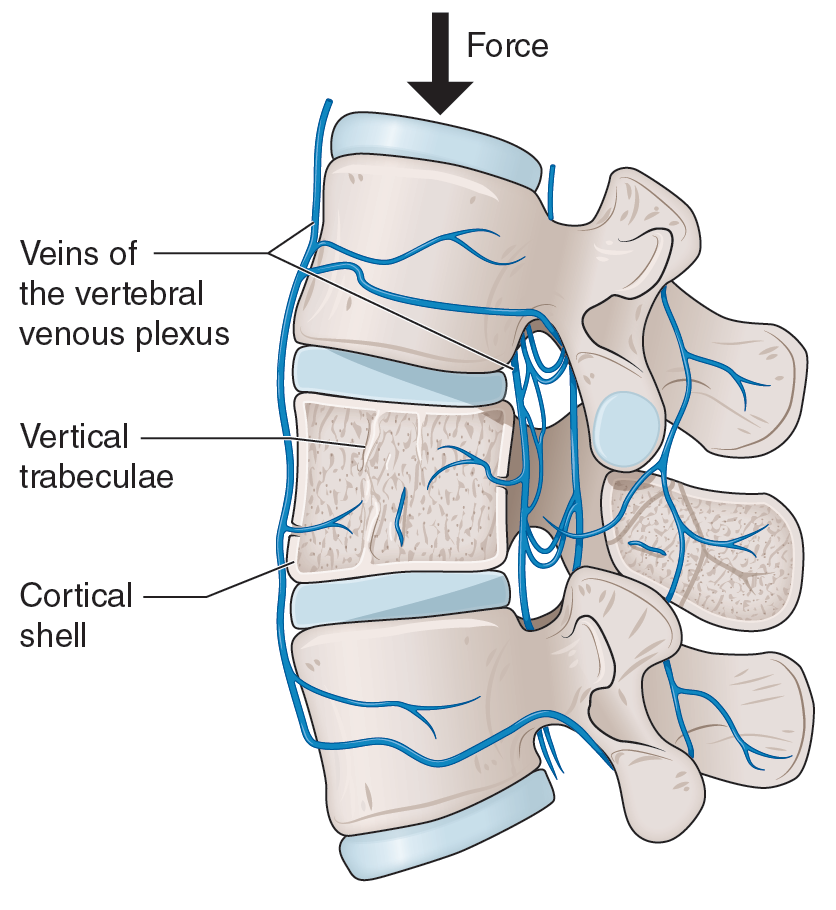

Medical Illustration

All images are works made for hire and are the exclusive property of the client. These are shown as sample purposes of my work only. For licensable work, please see my Illustration Services page.

Medical Illustrator for Precision Graphics, Lachina, and Human Kinetics Publishing (current)

Contract freelancer for many others, some examples of my work below.